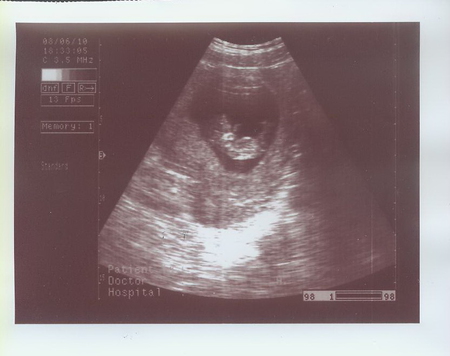

Были на УЗИ 08.06.2010 в МедЦентрСервисе на Курской. Очень понравилось.

С малышом все в порядке, размеры соответствуют норме. Толщина воротниковой зоны 1мм.

Сказал, что Малыш непоседа :) Кувыркался там, как акробат настоящий :)

Срок по УЗИ - 10 недель 3 дня.

Распечатал три фотографии!